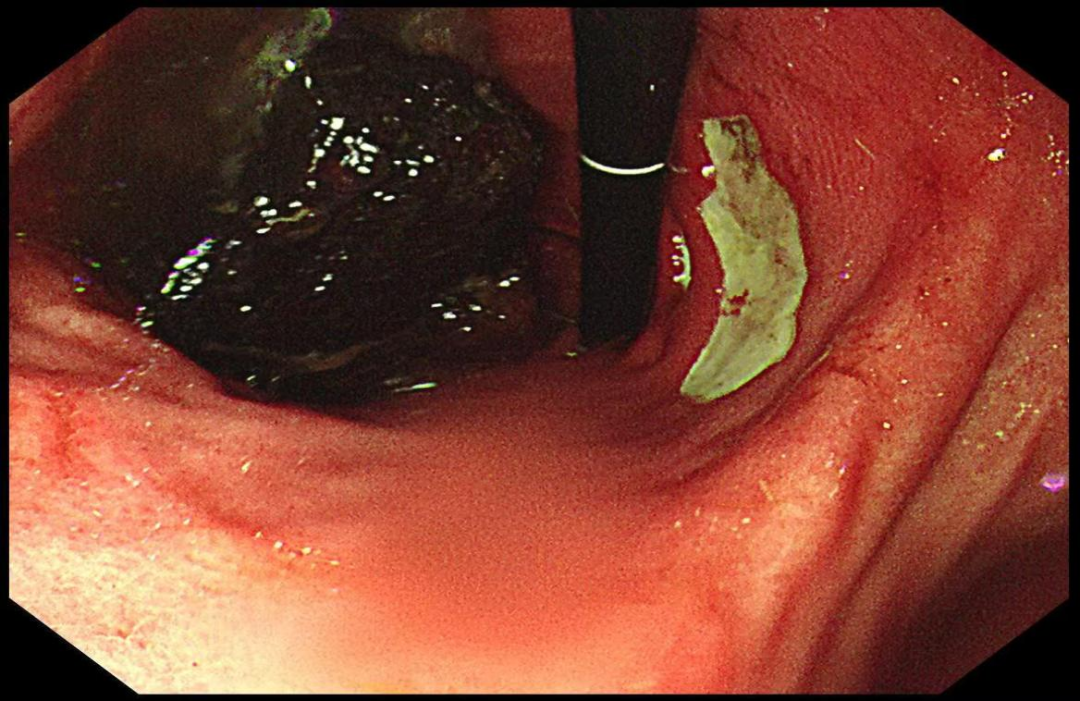

饮食习惯与健康息息相关,有时一些看似普通的食物也可能带来意想不到的健康隐患。近日,赵女士(化名)因贪嘴食用山楂球,导致胃结石发作,被紧急送往医院。经过胃镜检查,医生发现她的胃内形成了巨大的结石,并引发了胃溃疡。令人惊讶的是,医生的治疗方案中竟然包括喝可乐。

胃镜下明确诊断后,医生根据赵女士的饮食情况,开具了“可乐疗法”和治疗溃疡的药物。医生特别提醒,并非所有胃结石都适合通过喝可乐解决,尤其是那些“大而硬”的结石,可能需要内镜甚至手术干预。此外,糖尿病、痛风、心脏病患者以及胃部有溃疡、糜烂的患者,不适用“可乐疗法”。

图片来源:内镜中心提供,严禁转载